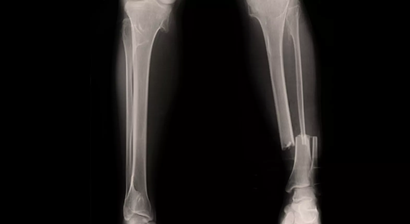

Unterschenkel Marknagel

Der Unterschenkel besteht aus dem Schien- und Wadenbein (Tibia und Fibula). Kommt es zu einem Unterschenkelbruch, sind meist beide Knochen gebrochen. Natürlich kann die Fraktur auch nur einen der beiden Röhrenknochen betreffen. Als Marknagelung oder Marknagelosteosynthese wird das Operationsverfahre...